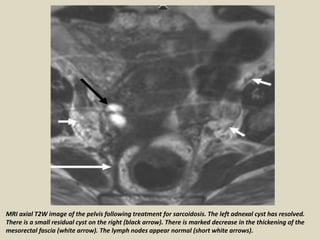

Sarcoidosis with bilateral adnexal cystic masses are demonstrated (black arrows). The cyst

wall on the right side is thick and irregular. There is marked thickening of the mesorectal

fascia (long white arrow). Multiple prominent nodes are demonstrated along the pelvic

sidewalls, which are very high in signal intensity on T2W (short white arrows).

MRI axial T2W image of the pelvis following treatment for sarcoidosis. The left adnexal cyst has resolved.

There is a small residual cyst on the right (black arrow). There is marked decrease in the thickening of the

mesorectal fascia (white arrow). The lymph nodes appear normal (short white arrows).